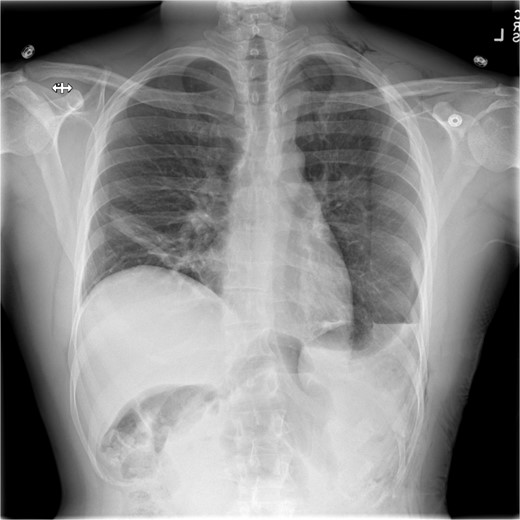

This is a case of a 26-year-old male patient who presented with symptoms of dyspnea on exertion, left chest pressure, and constipation for 7 years. He was a never smoker with no history of trauma, nor prior neck and chest surgeries. Baseline pulmonary functions tests revealed FEV1 of 71% predicted and DLCO of 77% predicted. Work-up included a computed tomography (CT) of the chest which revealed marked left hemidiaphragm elevation with compression atelectasis of the left lower lobe (Fig. 1). A fluoroscopic sniff test showed paradoxical movement of the left hemidiaphragm consistent with diaphragmatic paralysis. Interestingly, abdominal imaging obtained 14 months before surgery showed a displaced stomach but without volvulus (Fig. 2). Due to the impact on the patient’s quality of life, he was offered surgical treatment with a robotic-assisted left thoracoscopic plication of the diaphragm. This was done using a three-arm technique using the Da Vinci Xi surgical system (Intuitive Surgical, Sunnyvale, CA) with an additional assistant port. Plication was performed by placing multiple horizontal mattresses sutures reinforced with pledgets in an anterior–posterior orientation, and systematically working medial to lateral. A postoperative chest X-ray showed a satisfactory result (Fig. 3).

Pre-operative imaging revealing marked left diaphragm eventration.